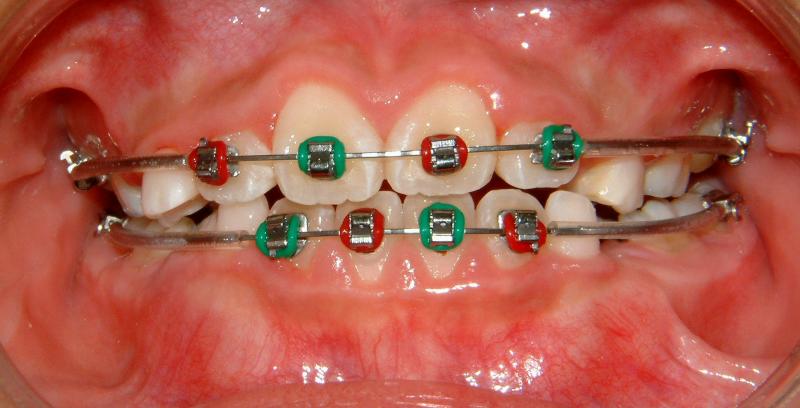

Case 1: 9 yr-old female

Fig. 2 View showing progress (after 2 month)